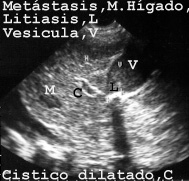

También hubo un caso, en que el hígado tenía una lesión ocupante de espacio que correspondía a una metástasis (Fig 11).

11LITIAM.JPG (19380 bytes)

Fig 11

La autopsia no la encontró porque quedó oculta en el interior de las secciones macroscópicas del hígado, por lo que concluyó que solo había diseminación a ganglios linfáticos regionales del carcinoma de colon que era la enfermedad fundamental del paciente. Análogamente no fueron encontrados en la autopsia granulomas calcificados hepáticos y esplénicos en un paciente con historia de tuberculosis miliar (Fig 12).En la imagen se observan como nódulos redondos, hiperecogénicos (blanquecinos),

La patología en el hígado fue fácil de demostrar. Como ejemplos presentamos las figuras 15, 16 y 17 de cirrosis, cirrosis con hepatocarcinoma y de metástasis tumoral.

15CIRROS.JPG (21095 bytes)

Fig 15

17METASH.JPG (44335 bytes)

Fig 17

En el cadáver la vesícula casi siempre esta llena de bilis que puede ser aspirada. Cuando hay cálculos los movemos con la punta de la aguja para ver si están enclavados y tomar muestras de esa zona (FIG 18).

18BILILI.JPG (21003 bytes)

Fig 18

Por otra parte la ecopsia puede medir conductos como la vena porta y el tracto biliar que pueden estar dilatados expresando cambios funcionales (Fig 19).

19TRACTO.JPG (26333 bytes)

Fig 19

Esta medida no es posible hacerla en la autopsia porque la naturaleza elástica de la pared nos puede falsear variaciones de milímetros.